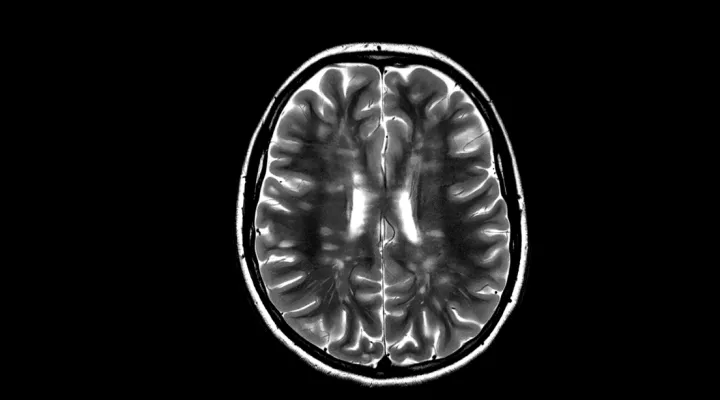

Multiple Sklerose (MS) und entzündliche Erkrankungen des zentralen Nervensystems (ZNS)

Die Multiple Sklerose (MS) ist eine chronische entzündliche Erkrankung des Gehirns und des Rückenmarks.

Manchmal tritt sie bereits bei Kindern und Jugendlichen auf. Erste Symptome sind innerhalb von Stunden bis Tagen auftretende Funktionseinschränkungen wie eine Sehminderung, Schwindel, Gefühlsstörungen oder eine Schwäche. Eine umfassende Abklärung und Abgrenzung von anderen entzündlichen Erkrankungen des Gehirns ist wichtig, um die richtige Therapie einzuleiten und Verlauf und Prognose zu verbessern. Bei der MS ist eine Dauertherapie notwendig, bei einigen anderen entzündlichen Erkrankungen reicht eine kürzere Behandlung aus.